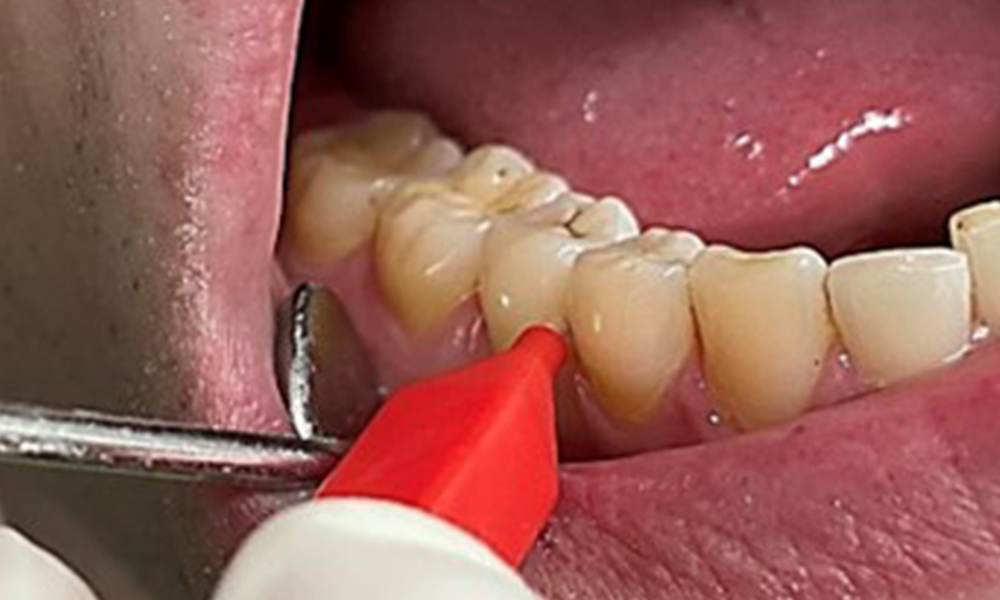

Поради иначе благоприятното общо медицинско състояние, нуждите, определени по време на оралния преглед, ще бъдат решаващи за лечението. От съществено значение ще бъде периодичното определяне на дълбочината на сондиране. Гингивалното кървене намалява при пушачите, поради което клиничната диагноза на пародонтита може да се постави само чрез сондиране (фиг. 7). Поставянето на изключителен акцент върху определянето на индексите на кървене може да замъгли съществуващ пародонтит или гингивит. (5)

Инструкциите и мотивацията са важни компоненти на тези срещи. Доброто поведение и разбиране на оралната хигиена в домашни условия са важни за пациентите. Натрупването на зъбна плака е особено видимо в цервикалните области (фиг. 8).